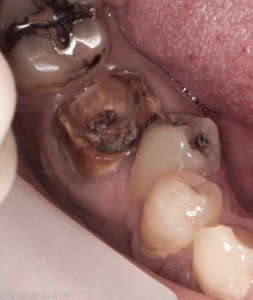

仮ぶたが取れてしまうとその周囲はあっという間に虫歯になってしまいます。

痛くないからいいかと放置すると虫歯が進行してそのことが原因で抜歯に至るケースもあります。

根管周囲の軟化象牙質(虫歯)をきれいに除去し隔壁を作成する必要があります。隔壁をきちんと作成することでで根管内部に細菌の侵入が起こらなくなり、ラバーダムなどの器具がかかるようになります。

細菌の侵入と汚染によって根管内部はボロボロの状態でした。

根管周囲の象牙質にも細菌の侵入が認められ真っ黒になった象牙質がボロボロと取れていきます。

健康な象牙質が薄くなり被せものをかぶせた後に咬合力で歯根破折を起こしてしまう可能性があります。